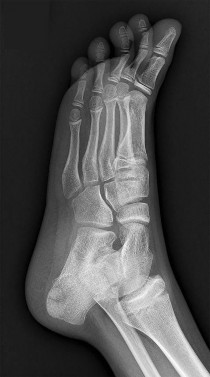

A 14-year-old boy complains of a painful, rigid flatfoot and a history of recurrent ankle sprains. Physical examination demonstrates severe restriction of subtalar motion and peroneal spasticity. A 45-degree internal oblique radiograph of the foot reveals an 'anteater nose' sign. Which of the following is the most likely diagnosis?

A 13-year-old male presents with recurrent ankle sprains and a rigid, painful flatfoot. Radiographs show an elongated anterior process of the calcaneus resembling an "anteater's nose" on the lateral view. What is the most likely diagnosis?

A 12-year-old boy presents with a history of recurrent ankle sprains and a rigid, painful flatfoot. Radiographs demonstrate an "anteater nose" sign.

Which radiographic view is most sensitive for confirming the exact location of the most likely coalition?